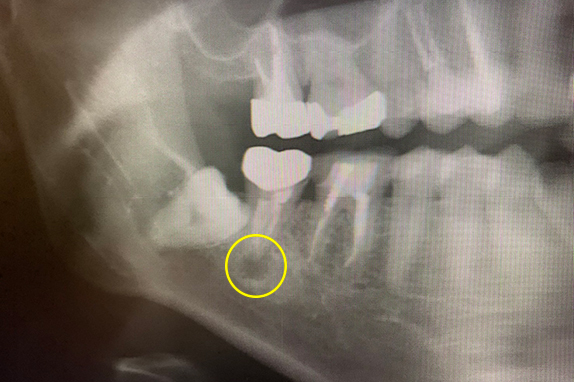

CASE 07 マイクロエンド(精密根管治療)+歯根周囲掻爬(歯周外科)

-

- 主訴

- 歯ぐきがよく腫れる(10代女性)

-

- 回数期間

- 7回 約1年半

-

- 治療法

- マイクロエンド(精密根管治療)、歯根周囲掻爬(歯周外科)

-

- 治療費用

- 約35万円(税抜)

歯ぐきがよく腫れる主訴で来院。レントゲン写真の術前を見ると大きな影が確認できます。この部分に嚢胞(のうほう)がある状態です。マイクロエンドと歯根周囲掻爬(歯周外科)をすることで改善したケースです。

<リスク・副作用>

治療後は痛み、腫れ、痺れなどの副作用が生じる場合があります。症状が再発する可能性があります。